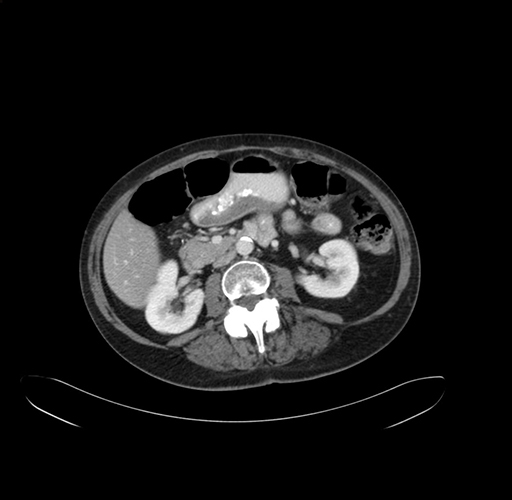

Axial Venous